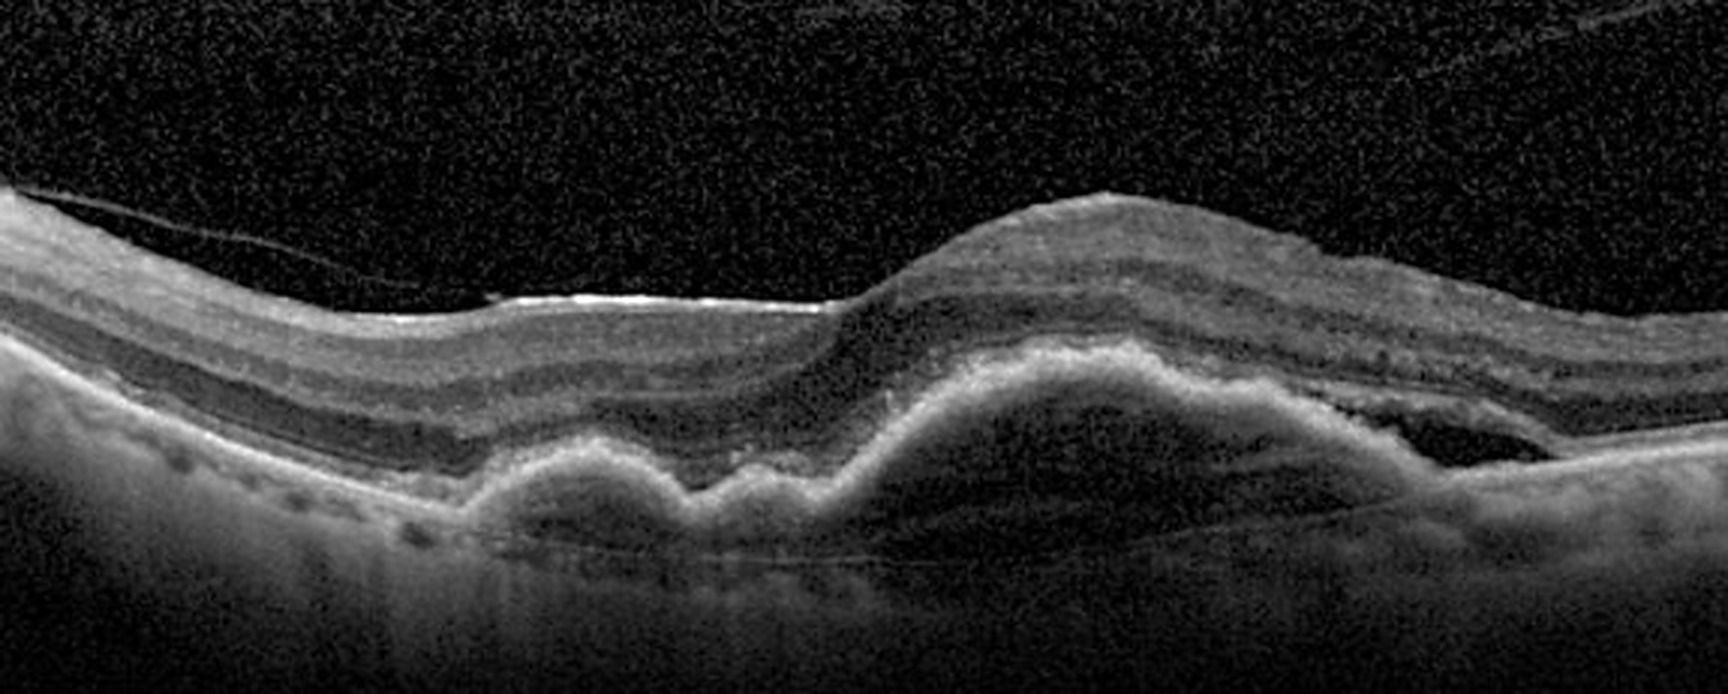

La dégénérescence maculaire liée à l'âge DMLA exsudative est une maladie chronique avec une activité cyclique présentant des périodes de rémission. Il n'existe pas de guérison possible. Une atteinte bilatérale est fréquente.

Il est donc nécessaire de reconnaître une DMLA pouvant bénéficier d'une prise en charge mais également d'identifier une vasculopathie polypoïdale choroïdienne afin d'adapter au mieux la prise en charge du patient.

Le but de cette formation est de montrer comment adapter le nombre d'injection intra vitréenne d'anti-VEGF en s'adaptant à la pathologie, au patient et à la molécule choisie afin de limiter les risques liés à ces IVT.